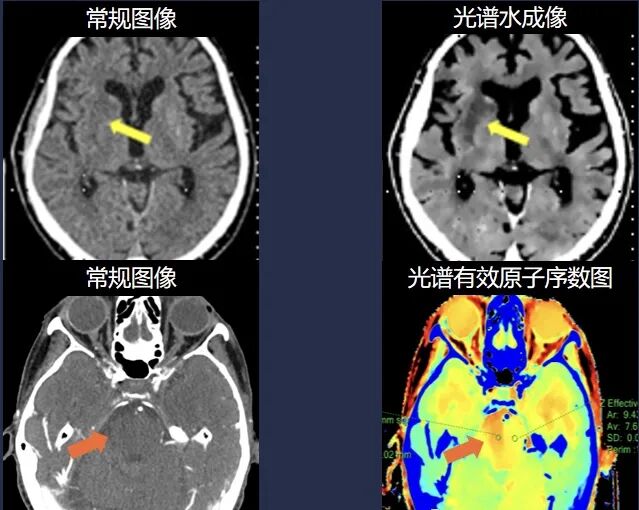

突破单参数常规CT极限,多参数全流程卒中关护

皓克CT平扫检出超急性期缺血性卒中及出血性卒中,CTA扫描可以同时得到脑血管、脑灌注、活动性出血等多重信息,避免重复检查,帮助病患的争取宝贵时间,及时得到救治,挽救患者生命。